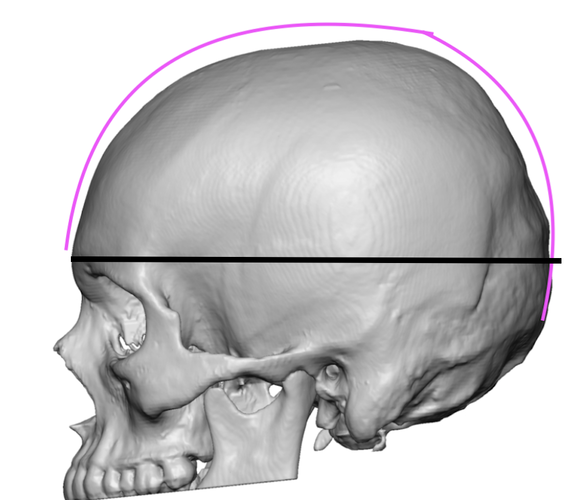

This is normal skull:

This is normal skull:

Do you notice the difference??

my maxilla itself isn't really short but bone above upper teeth specifically Alveolar process of the maxilla is extremely short compared to normal.